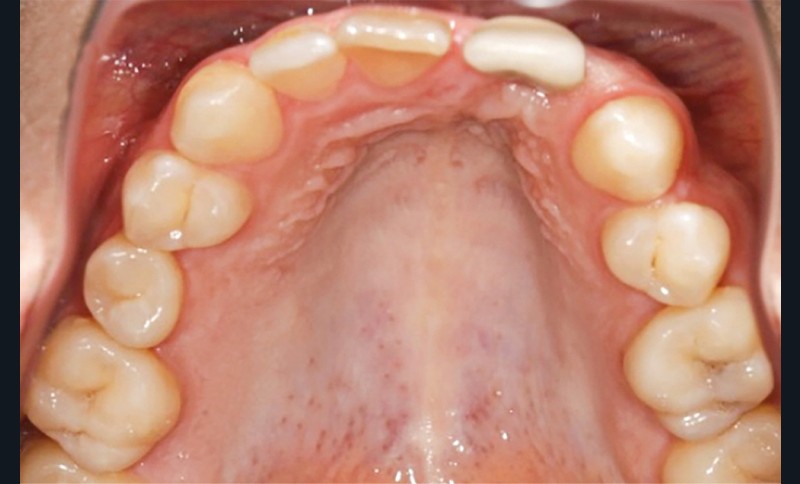

- au niveau dentaire : une arcade maxillaire asymétrique avec déviation du milieu maxillaire à gauche. On note l’absence de 21, 22, 25, 35 et 45, une classe II droite et gauche avec infraclusion antérieure et la présence d’un implant en place de 21 avec un diastème de 3 mm entre 21 et 23 (fig. 3) ;